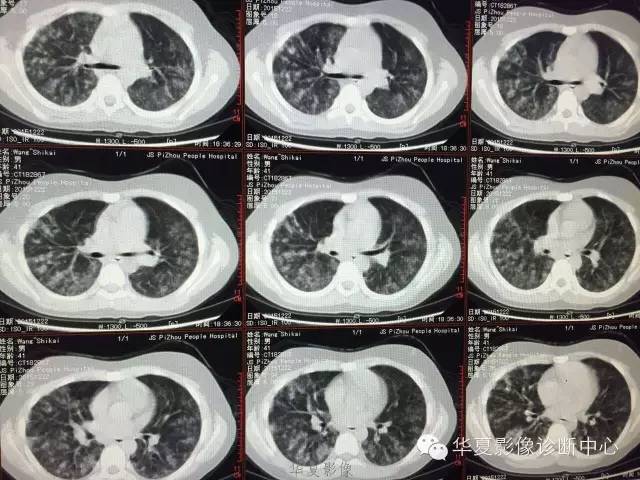

支原体肺炎1例CT影像表现

【病例】支原体肺炎1例CT影像表现